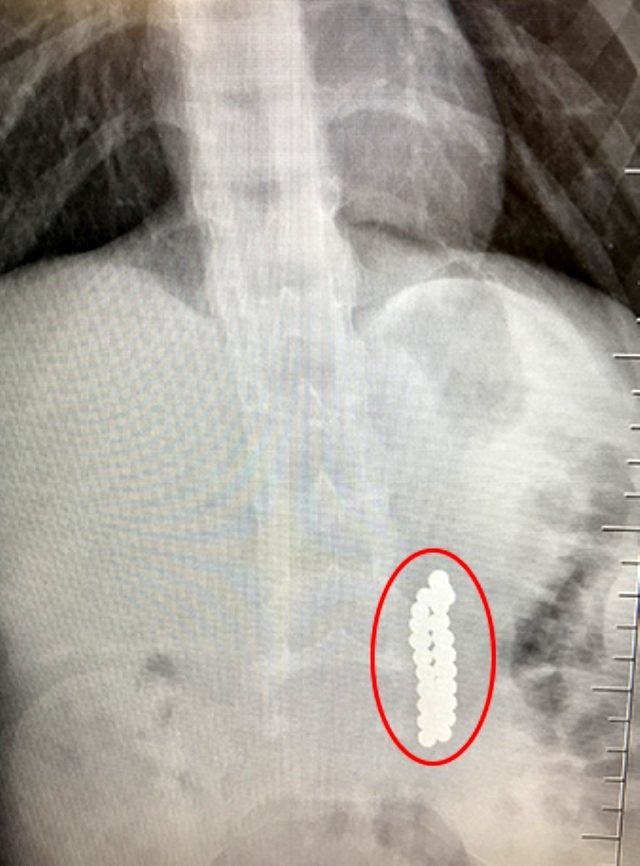

Beylikdüzü'nde 9 yaşındaki bir çocuk ailesinin haberi olmadan neodyum adı verilen stres bilyeleri olarak da bilinen 42 adet mıknatısı yuttu. Birkaç gün sonra şiddetli karın ağrısı ve kusma şikayeti ile hastaneye gelen çocuğun röntgeni çekildi.

Röntgen filminde çocuğun midesinde boncuklar halinde yabancı bir cisim tespit edildi. Bağırsağını delen cismi fark eden Beykent Üniversitesi Çocuk Cerrahisi Uzmanı Prof. Dr. Ali Çay çocuğu ameliyata aldı. Yapılan ameliyatta çocuğun bağırsaklarından rengarenk şekilde 42 adet neodyum çıkarıldı.

Konuyla ilgili konuşan Prof. Dr. Çay, yutulan cisimlerin normalde sindirim sistemi ile çıkabileceğini ancak çoklu mıknatısların bağırsaklarda delinmeye neden olabileceğini ifade ederek, "Bizim hastamız yaklaşık 42 tane bu mıknatıstan yutmuş çeşitli hastanelere müracaat etmiş. Burada yapılan incelemelerde çekilen filmlerde tesadüfen bu mıknatısları yuttuğunu biz radyografide gördük hastamızı ameliyata aldık. İnce bağırsak uç kısmında delinme oluşturmuştu. Biz bu mıknatısları çıkardık" dedi.